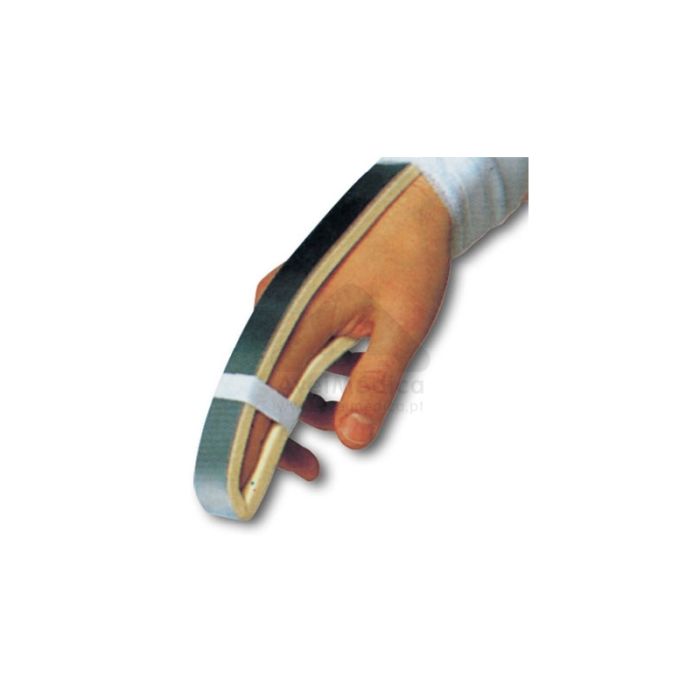

TALA DEDO ALUMINIO EM U ZIMMER – T.M

TALA DEDO ALUMINIO EM U ZIMMER – T.M